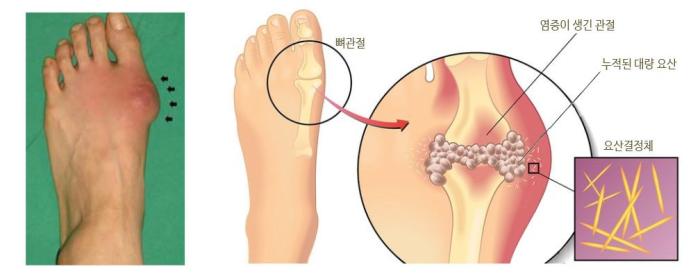

통풍 환자에서는 혈액 내 요산이 지나치게 많아서 이것이 결정체로 변하고,

이 요산 결정체가 관절 내에 침착하여 염증을 유발하게 되는 것입니다.

통풍성 결절이라 불리는 덩어리가 관절 주위나 피하조직에 나타나기도 하며,

1) 주로 엄지발가락, 발목, 무릎 등 한군데 관절이 갑자기 빨갛게 부어오르고

4) 가장 특징적으로는 엄지발가락 관절에 잘 발생하며